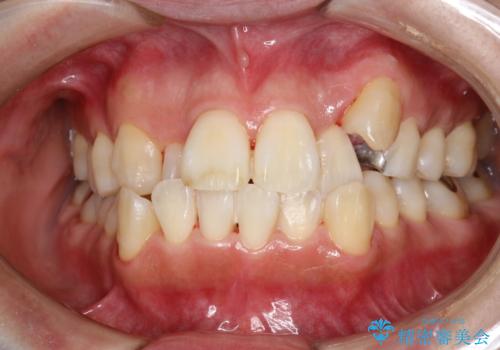

- これから矯正治療を始めるため、今の状態でも歯をきれいにしておきたいとのことでした。PMTC60分コースを行いました。

プラーク(細菌の塊)や歯石がたまると歯の表面はザラつきいてきます。そのザラつきは歯周病や虫歯菌の棲家となります。そのまま放置すると、歯肉が腫れてきたり、歯肉から出血したり、口臭が強くでたりします。とくに歯肉の境目は、歯磨きで汚れを除去することが難しく、プラーク(細菌の塊)や歯石が溜まりやすい場所です。

歯並が、がたついている場合はなおさら汚れが溜まりやすいです。矯正治療前や矯正中、定期的にPMTCをすることで、矯正治療中の歯肉トラブルを防ぐことにつながります。